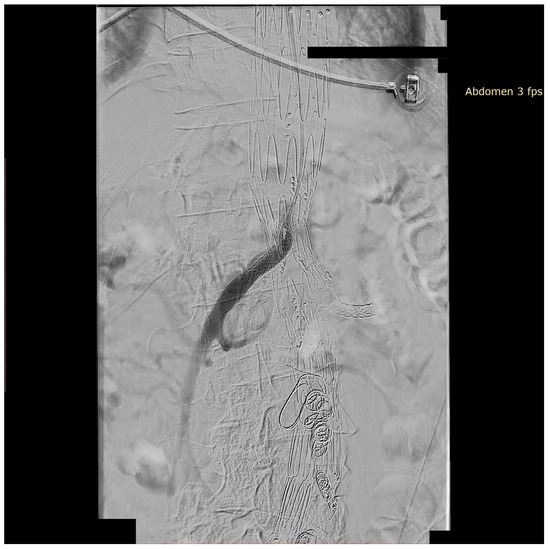

We present the case of an 82-year-old male patient who appeared in the emergency department due to progressive weakness and abdominal pain (2024). Due to a drop in blood pressure to 80/40 mmHg, a continuous infusion of norepinephrine was initiated. The hemoglobin level was approximately 5.1 g/dL. His medical history included generalized atherosclerosis, renal failure, and a thoracoabdominal aortic aneurysm (TAAA) treated with endovascular aneurysm repair (EVAR) using stent-graft implantation 4 years earlier (2020). At that time, the angio-CT scan revealed an aneurysm starting just below the celiac trunk, extending to the superior mesenteric artery (SMA) and both renal arteries (RAs). The maximum diameter of the aortic aneurysm was 51 mm; however, the left common iliac artery measured 41 mm in diameter, an indication for thoracoabdominal stent graft implantation. The aortic aneurysm itself was completely free of mural thrombus. The patient had also experienced a heart attack 16 years earlier and a transient ischemic attack (TIA) 2 years earlier. Following the stent graft implantation, he underwent multiple successful interventions to address endoleaks. One year after implantation, endovascular treatment with embolization coils was performed to eliminate leakage from the lumbar artery (LA) (2021). Three years post-implantation, he was admitted to address leakage from the inferior mesenteric artery (IMA) using embolization coils as well (Figure 1) (2023). In 2024, an X-ray and CT scan revealed a rupture in a branch of the stent graft located in the SMA in its middle part, along with an enlarged aneurysm sac (74 mm) due to the fracture and leakage (Figure 2, Figure 3, Figure 4 and Figure 5). The angio-CT scan did not reveal any contrast extravasation beyond the vessel wall. However, significant contrast leakage was visible in the area of the visceral arteries within the aneurysm sac. The implanted device was the Zenith t-Branch Thoracoabdominal Endovascular Graft, and the ruptured branch was identified as the Bentley BeGraft (Bentley InnoMed GmbH, Hechingen, Germany). Urgent surgical intervention was performed. Intraoperative angiography (IA) showed a breach in the continuity of the BeGraft material within the SMA, with contrast leakage into the aneurysm sac (Figure 6 and Figure 7). To address the leakage and restore the continuity of the SMA branch, an additional BeGraft Plus 8 × 57 mm was implanted into the damaged branch. Subsequent IA and control CT scans confirmed the elimination of leakage, restoration of stent graft continuity, and revascularization of the SMA (Figure 8, Figure 9 and Figure 10). The surgery was completed without complications, and the patient was discharged home in good general condition. The patient returned for follow-up 3 weeks after the last intervention. An angio-CT examination was performed, revealing no enlargement of the aneurysm sac (74 mm), confirming the elimination of the endoleak, and demonstrating successful revascularization of the SMA. Ongoing follow-up will be continued.

Figure 8. Successful SMA revascularization after BeGraft implantation. No visible contrast leakage. Intraoperative angiography.

Figure 9. Repaired superior mesenteric artery branch of stent graft in three planes. The mended site is centrally located at the intersection of the lines defining the planes and additionally marked with green arrows. Panel (A)—sagittal projection, panel (B)—axial projection, panel (C)—coronal projection. Control Angio-CT 3D MPR, arterial phase.